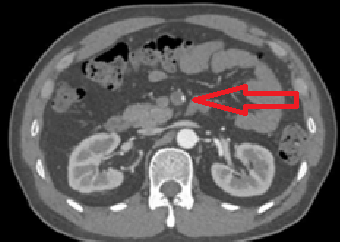

CT: Superior mesenteric artery obstruction

급성 복통 및 혈변을 호소하는 Afib환자의 복부CT상 상장간동맥의 폐쇄가 확인되므로 상장간동맥색전(SMA embolism)으로 진단한다.

• 추가적으로 시행한 복부 CT상에서 상장간동맥(SMA)의 폐쇄가 관찰된다.

• 급성적인 복통 및 혈변을 호소하는 AF 환자에게서 복부 CT상 상장간동맥의 폐쇄가 확인되므로 상장간동맥색전(SMA embolism)으로 진단한다.